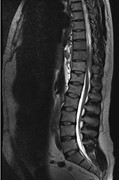

Primary spinal epidural Hodgkin's lymphoma

Onur Yaman and others

Journal of Surgical Case Reports, Volume 2013, Issue 10, October 2013, rjt090, https://doi.org/10.1093/jscr/rjt090